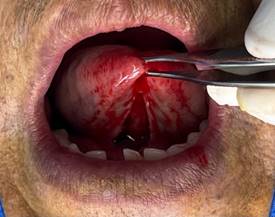

· Desprendimiento nítido del frenillo: Al terminar la primera fase de la diéresis se debe observar el desprendimiento nítido de la inserción del frenillo. Con este desprendimiento se intenta evitar la recidiva. (Figura 5)

Figura 5. Desprendimiento nítido del frenillo.

Elaboración: Los autores.